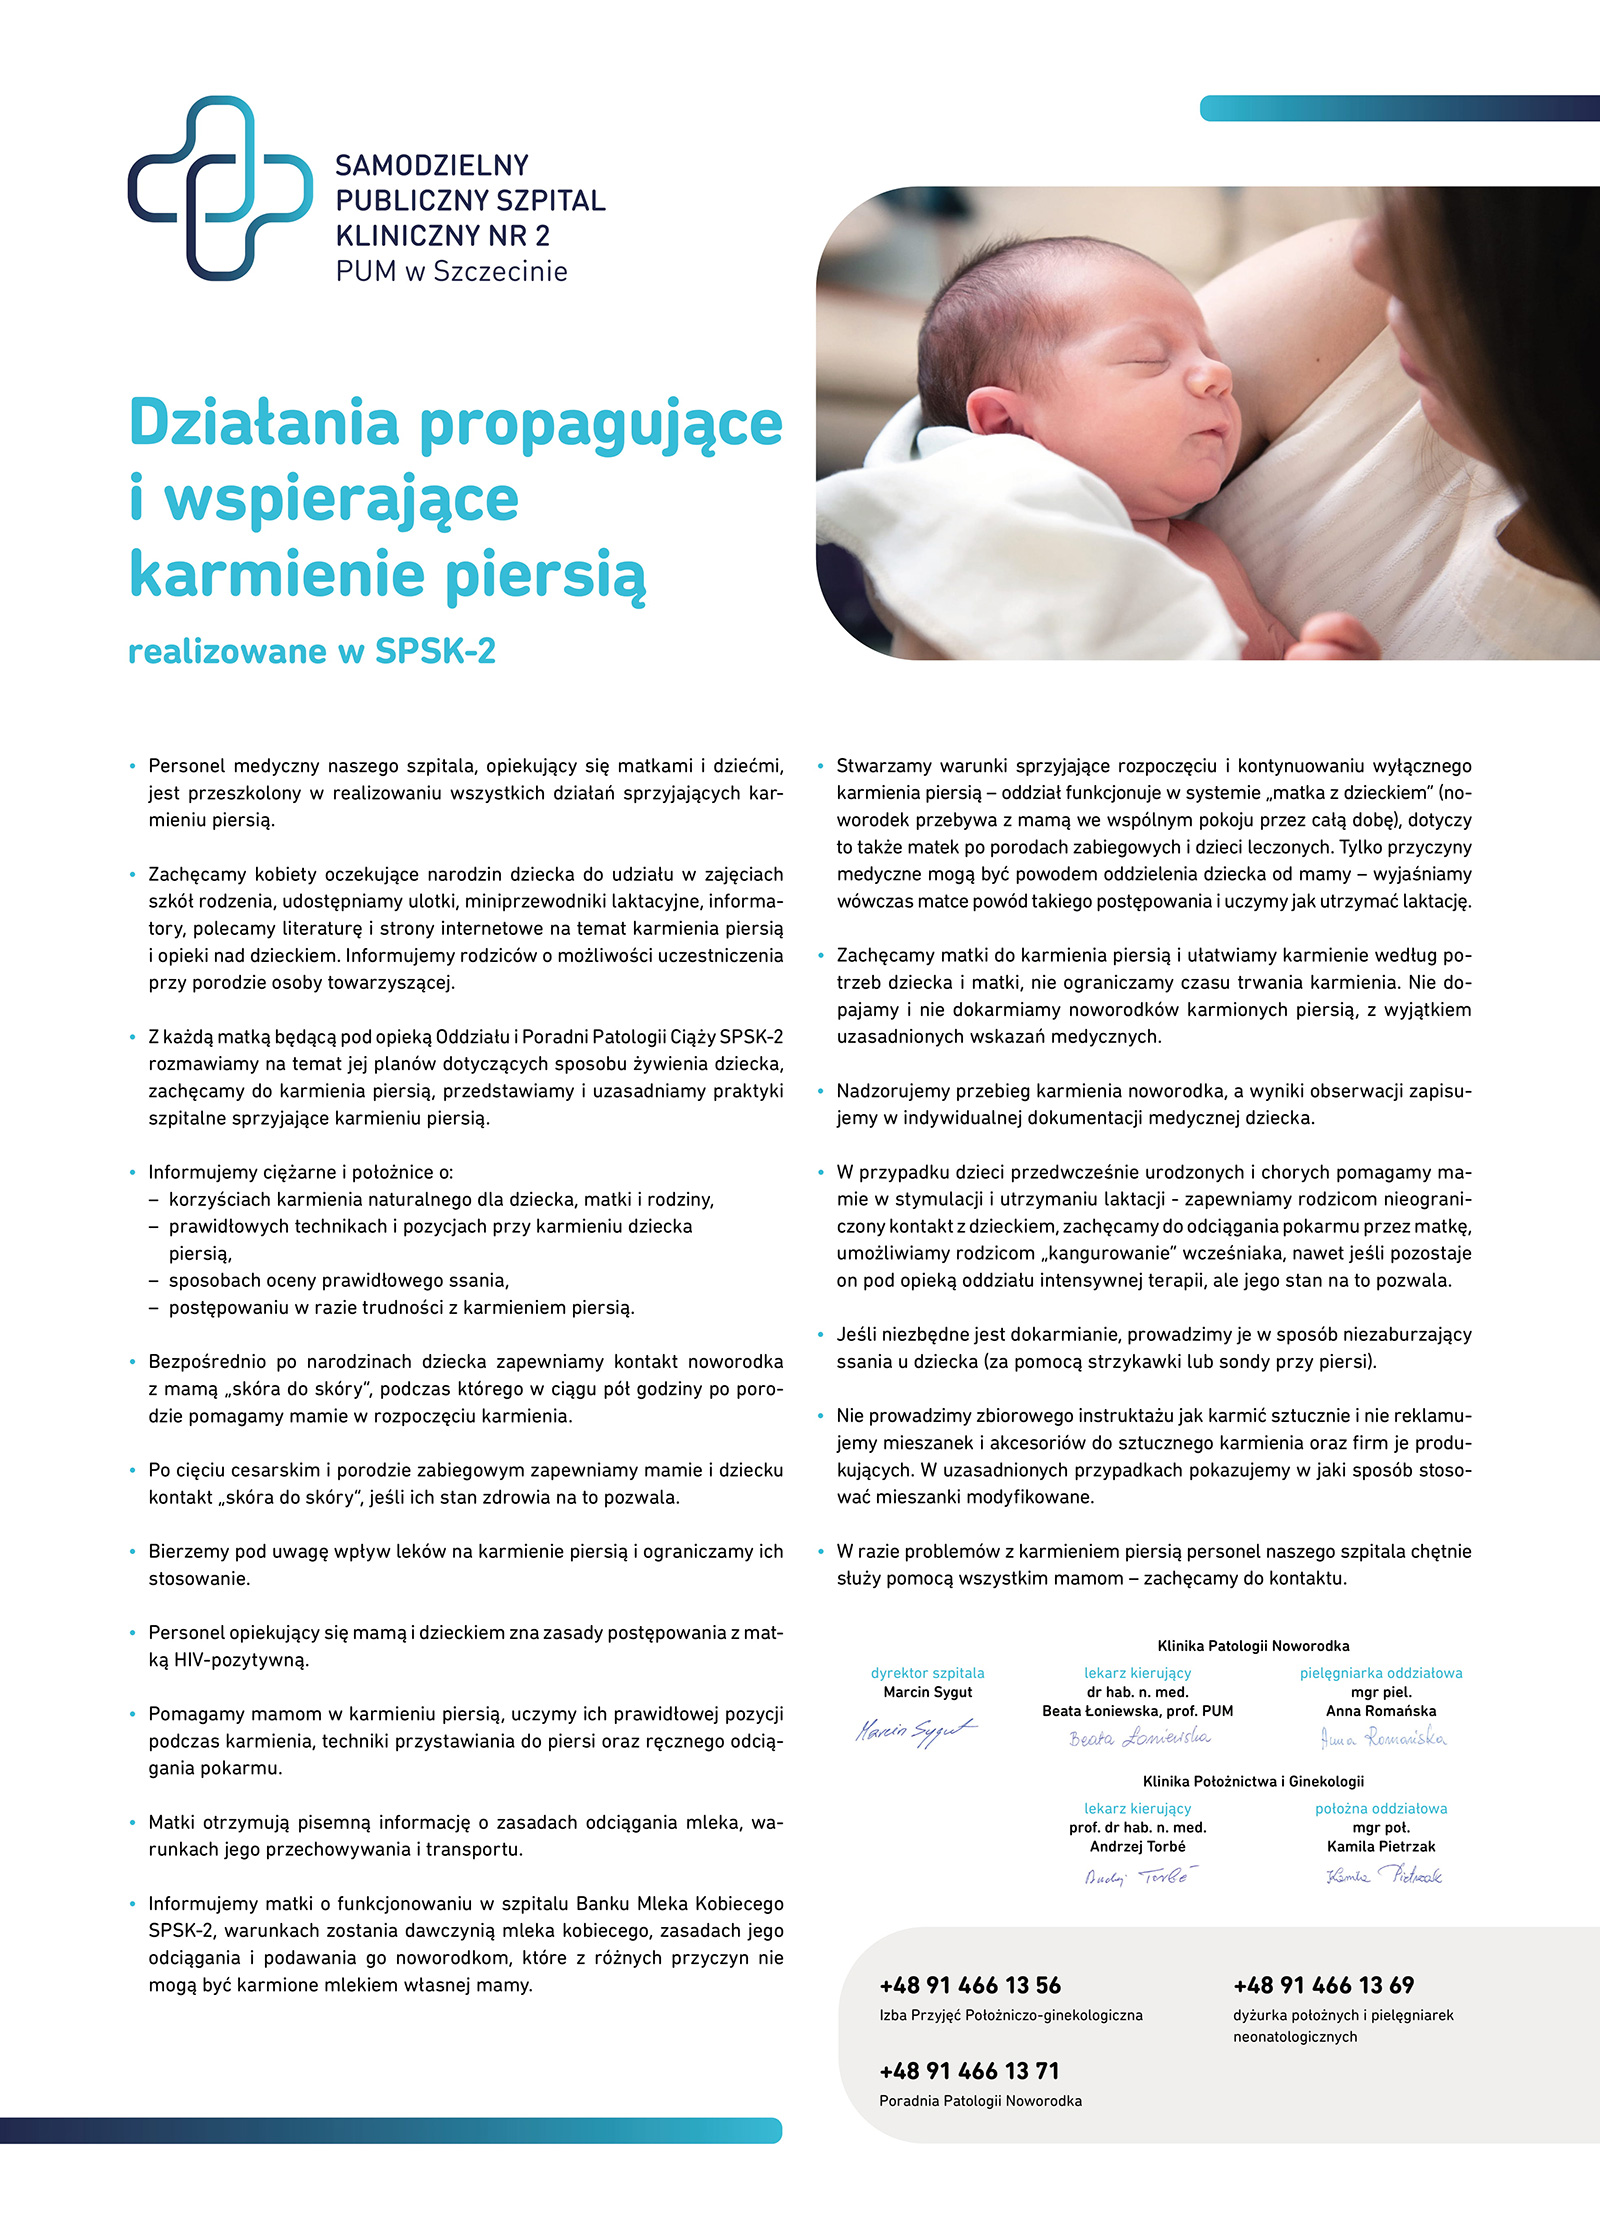

Sukces w rankingu Gdzie Rodzić po Ludzku

2023-01-18Jesteśmy w wojewódzkiej czołówce rankingu Fundacji Rodzić po Ludzku. Nasz szpital znalazł się w trójce najlepszych placówek w województwie zachodniopomorskim w Rankingu Szpitali Gdzie Rodzić po Ludzku.

To olbrzymi sukces zespołów naszych klinik: Położnictwa i Ginekologii oraz Patologii Noworodka.

Wyniki rankingu są pochodną wypełnionych przez pacjentki anonimowych ankiet, które rodziły na oddziale siłami natury lub poprzez cesarskie cięcie. Ankiety zawierają pytania dotyczące m.in. przygotowania do porodu, doświadczenia z izby przyjęć, przebiegu porodu, pobytu na oddziale położniczym, odczuć pacjentki związanych z podejściem personelu do niej, sposobu traktowania oraz komunikacji z pacjentką.

Pracę i zaangażowanie naszych zespołów szczególnie doceniono w takich obszarach jak:

- wsparcie w karmieniu piersią

- zadowolenie z opieki

- kontakt z dzieckiem po narodzinach

- postawa personelu

- realizacja praw pacjenta.

Co roku na świat w Klinice Położnictwa i Ginekologii przychodzi na świat ponad 2 000 dzieci. Jest wśród nich wiele bliźniąt, a także trojaczki. Klinika oferuje realizuje pełen zakres diagnostyki i terapii w zakresie położnictwa, patologii ciąży oraz diagnostyki prenatalnej i genetycznej. Oddział Patologii Ciąży, Położnictwa i Ginekologii oferuje pełen zakres usług z dziedziny ginekologii operacyjnej. Klinika bierze udział w programie Koordynowana Opieka nad Kobietą w Ciąży (KOC).

W Klinice Patologii Noworodka realizowane są świadczenia wysokospecjalistyczne, w zakresie III stopnia referencyjności. Oznacz to, że Klinika jest przygotowana merytorycznie i wyposażona w odpowiedni sprzęt do ratowania dzieci urodzonych ze skrajnie małą masą ciała lub w ciężkim stanie ogólnym, dzieci z wadami wrodzonymi i innymi patologiami okresu noworodkowego.

Zespół Kliniki zajmuje się noworodkami, które urodziły się nie tylko w USK-2, lecz także w innych szpitalach o niższym stopniu referencyjności. Wśród łóżek dla noworodków funkcjonują miejsca w systemie rooming-in (system “matka-dziecko”, w ramach którego dziecko przebywa na sali razem z mamą, w swoim łóżeczku), a także miejsca dla wcześniaków i noworodków obserwacyjnych (wymagających stałej obserwacji personelu medycznego) oraz stanowiska intensywnej terapii.

Kompleksową opiekę nad mamą i dzieckiem dopełnia pomoc doradczyń laktacyjnych, które wspierają mamy w pracy nad laktacją, jej pobudzeniem i karmieniem noworodków naturalnym pokarmem. Mamy wcześniaków i chorych noworodków, które z przyczyn zdrowotnych nie mogą ich karmić swoim mlekiem, mogą korzystać z naturalnego pokarmu z Banku Mleka Kobiecego naszego szpitala, do którego honorowe dawczynie mleka oddają nadmiar swojego pokarmu dla innych, potrzebujących go dzieci.

Obecnie budynek klinik ginekologiczno-położniczo-noworodkowych jest w trakcie rozbudowy i modernizacji. Powstaje nowoczesny pawilon, w którym pacjentki będą miały zapewnione komfortowe warunki pobytu, leczenia, porodu i opieki nad dzieckiem. Natomiast już od wielu lat kadra tych oddziałów cieszy się bardzo dobrymi opiniami pacjentek. A to w rankingu doceniły ciężarne i świeżo upieczone mamy. Wszystkim członkom zespołów klinik: Położnictwa i Ginekologii oraz Patologii Noworodka gratulujemy i dziękujemy za pracę, serce, wiedzę i empatię.

Ranking jest inicjatywą Fundacji Rodzić po Ludzku. Celem rankingu jest promowanie szpitali, w których kobieta może urodzić „po ludzku” – z poszanowaniem jej godności, prywatności, gdzie w najwyższym stopniu przestrzegane są zapisy Standardu Organizacyjnego Opieki Okołoporodowej oraz Ustawy o prawach pacjenta i Rzeczniku Praw Pacjenta.